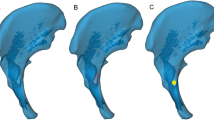

All lines generating the transition sequence 0-1-0 were registered as potentially valid screw tracks. Higher sequences (e.g., 0-1-0-1-0) represented breaks beyond the bone during the course through the IA region and were therefore excluded by the script. Because they were not surgically pertinent, potential entry points medial to the pelvic brim with screw tracks passing through the IA bone region were avoided. For this reason, 5 to 10 landmarks were set by mouse-clicks along the terminal line for each investigated acetabulum. Bresenham lines that passed the bone medial to these landmarks were excluded automatically. Furthermore, screw tracks along the quadrilateral bone stock beyond the fovea acetabuli throughout the posterior column were avoided by an iterative search operation of the program script that determined the thinnest point (PF) in the acetabular fossa as the cut-off (Fig. 3). The segmentation of the entirety of all the valid screw tracks constituted the secure IA bone corridor. At the initial run of the script, the Bresenham lines had a thickness of 0.5 mm (1 voxel). By enlarging the line diameter in 1-mm intervals, the spatial IA corridor volumes could be generated for the different screw diameters commonly used in surgical fracture fixation. As a final operation, the script computed the volumetric values of the 3-D corridor models, namely, the volume and the isthmus, entry, and exit areas for further statistical analyses.

All IA corridor volumes consistently showed a double-cone shape with the isthmus located in the region of the acetabular fovea as the limiting anatomical structure. The screw entry areas were projected to the iliopectineal eminence. The smaller the screw diameter, the more the shape of the entry area conformed to a teardrop. With increasing screw diameters, the shape thus became more spherical, and the corridor volumes decreased to a tubular shape. The exit areas were consistently localized to the sciatic protuberance. The surface of both areas mutually decreased with higher screw diameters (Fig. 4).